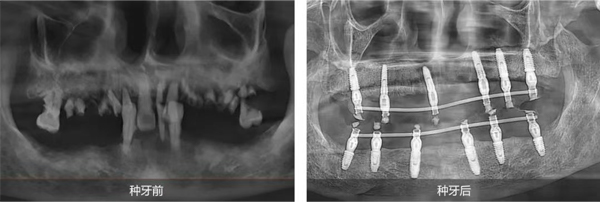

即刻種植 重煥口福

姜辰主任醫(yī)療團隊為陳叔叔定制了全口即刻種植修復方案。該方案既能滿足陳叔叔盡快恢復咀嚼功能的需求,又最大程度地減輕了他的痛苦,縮短了治療周期。手術在陳叔叔家人的陪伴下順利結束,當天,陳叔叔就戴上了臨時牙冠,恢復了基礎飲食功能。